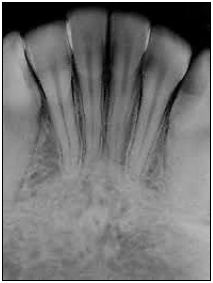

Observe a imagem a seguir.

Qual é a área radiografada mostrada na figura?